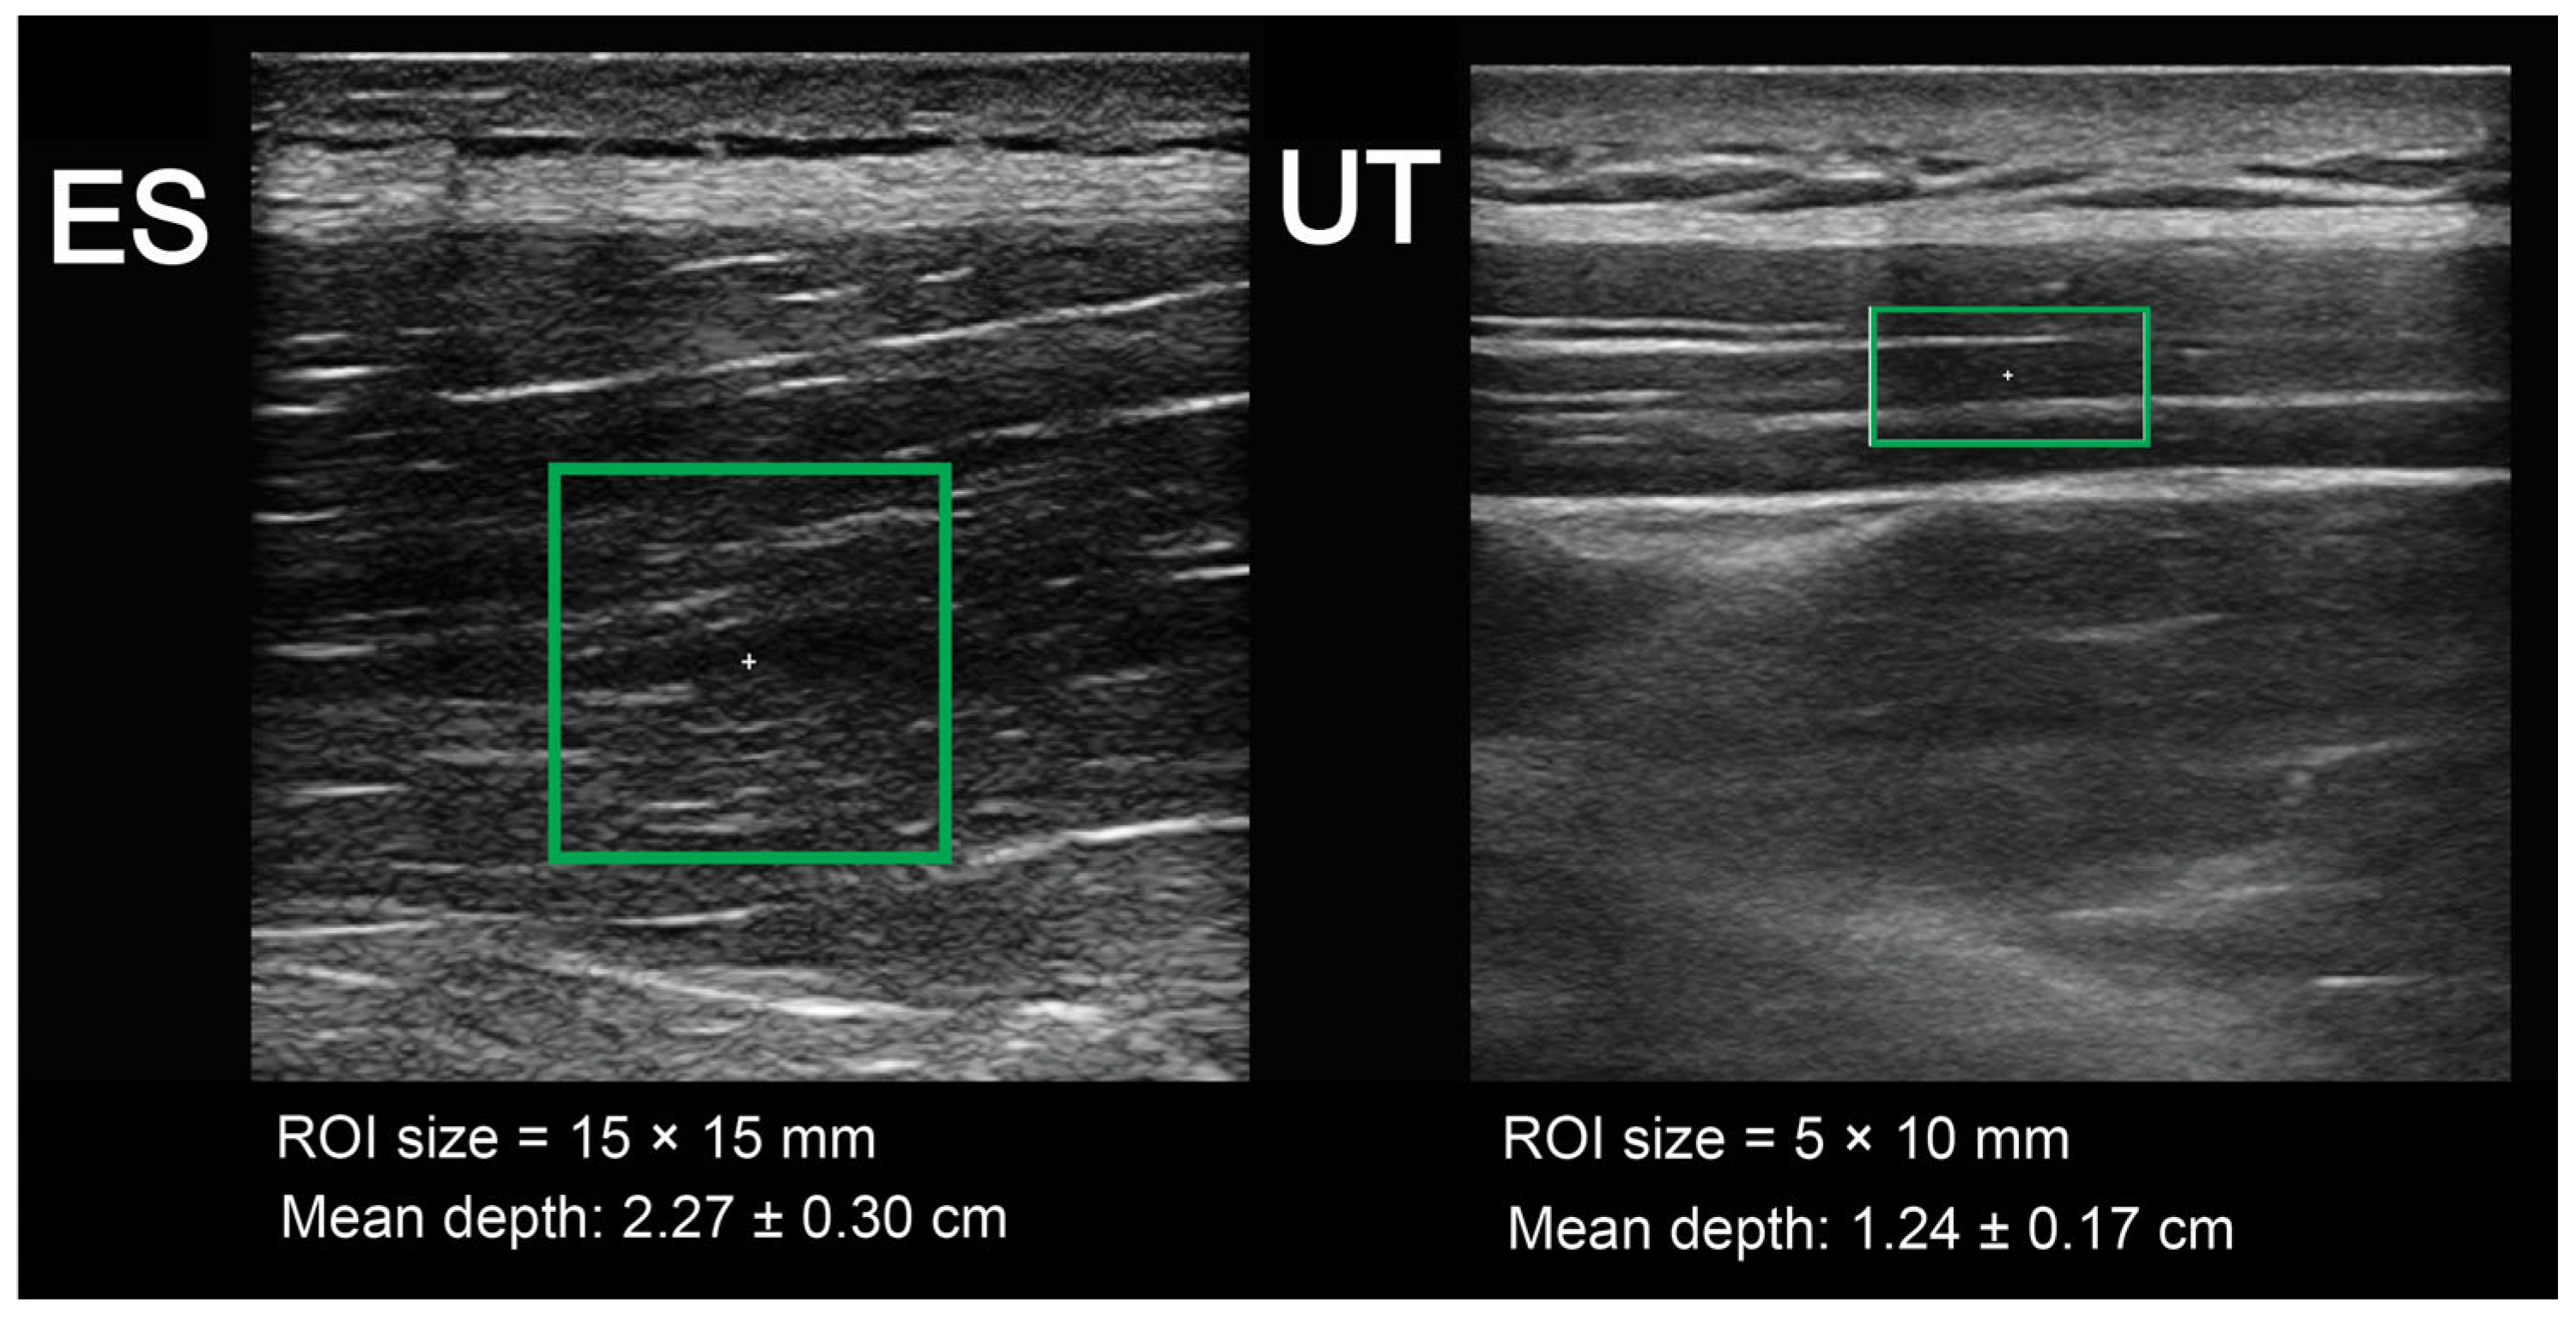

2.4. Muscle Stiffness Assessment